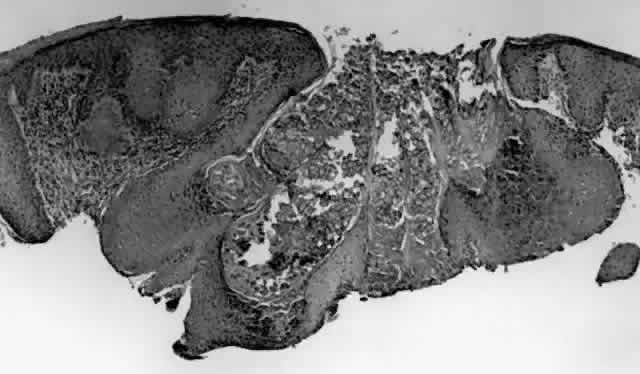

HPV-induced conjunctival squamous papillomas demonstrate papillomatosis, acanthosis, and koilocytosis (Fig. 6). Because they are mucous membrane lesions, those of the conjunctiva and lacrimal sac show no granular cell layer but will show keratinization if they are large or exposed (Fig. 7). In our experience the frequency of koilocytes is variable, even in lesions almost certain to be viral (Fig. 8). Scattered inflammatory cells may be present in the cores or epithelium. Virus can be detected immunohistochemically in the nuclei of the cells (Fig. 9).

Early dysplastic lesions (conjunctival intraepithelial neoplasia) show thickened epithelium with extension of basal-like cells beyond the basal layer, but cells continue to mature into flat squamous cells. Mitoses are also seen higher in the epithelium. As the degree of dysplasia worsens, the more superficial epithelium is replaced at higher levels by basal-type cells, mitoses can be seen further from the basal layer, and atypia of cells becomes more pronounced. With squamous cell carcinoma in situ, there is full-thickness dysplasia, cellular atypia is variable, and mitoses can be seen at all layers of the epithelium. Invasive squamous cell carcinomas are usually well differentiated. Pleomorphism, hyperchromaticity, dyskeratosis, and horn pearls are seen. Epithelial cell clusters can be seen invading below the basement membrane. Inflammatory cells are common in the substantia propria.

Squamous papillomas of the eyelid are exophytic lesions with multiple fronds, each showing acanthotic epithelium around a fibrovascular core. There is typically hyperkeratosis and koilocytosis. Inflammatory cells may be present.